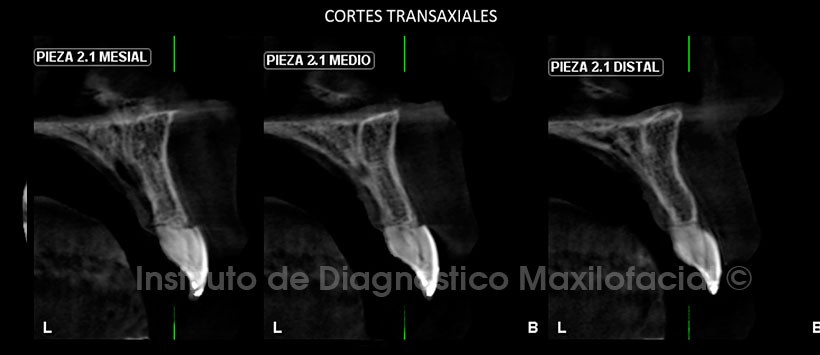

A la evaluación de la tomografía volumétrica (CBCT) en cortes axiales (Figura 2), transaxiales (Figura 3) y tangenciales (Figura 4), se evidencia reabsorción radicular externa severa de los dos tercios radiculares de la pieza 2.1 con pérdida total de soporte óseo, material de restauración en borde incisal y en la superficie palatina, presencia de cálculo en cámara pulpar. A nivel de la pieza 2.2 se aprecia leve reabsorción radicular externa a nivel apical y presencia de cálculo en cámara pulpar.